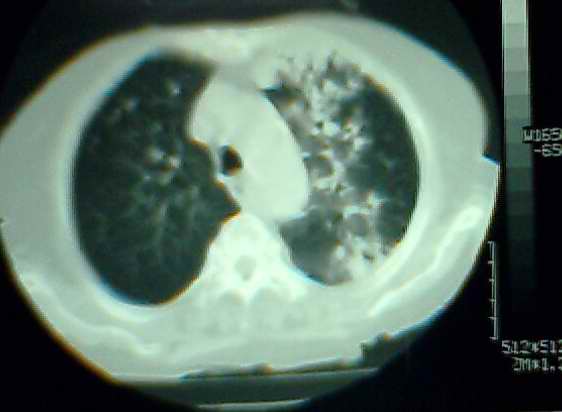

以上是2009-05-25的照片。

以下是引用hhx58在2009-9-11 19:48:00的发言:[br]有4个是心电监护的电极。[br]ct图片可见有肺气囊。但未拿到片上传。

以下是引用37度在2009-9-12 11:54:00的发言:[br][br] [br] 支气管扩张合并混合型感染 [br] [br]

以下是引用dyqct在2009-9-12 8:42:00的发言:[br]慢性支气管炎合并间质纤维化、肺气肿、支气管扩张、感染。建议ct进一步检查。

以下是引用黑白光影在2009-9-12 16:43:00的发言:[br]慢支并感染(霉菌?)